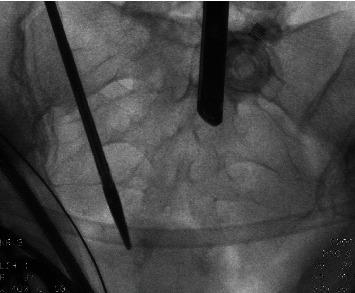

We present a case about Essure removal surgery in which the third markers of the device have torn off. The woman needed a second surgery for complete removal of the devices. Fluoroscopy during surgery is a good method to visualize the lost fragments. With fluoroscopy, a hysterectomy is not needed for complete removal. It is important to understand the structure of the device and to be aware of the four radiopaque markers during surgery and their removal.

我们介绍了一例关于取出Essure装置的手术病例,该装置的第三个标记物已脱落。该女性需要进行第二次手术以完全取出该装置。手术中的荧光透视是可视化丢失碎片的好方法。借助荧光透视,无需进行子宫切除术即可完全取出。了解该装置的结构并在手术过程中知晓四个不透射线的标记物及其取出情况非常重要。